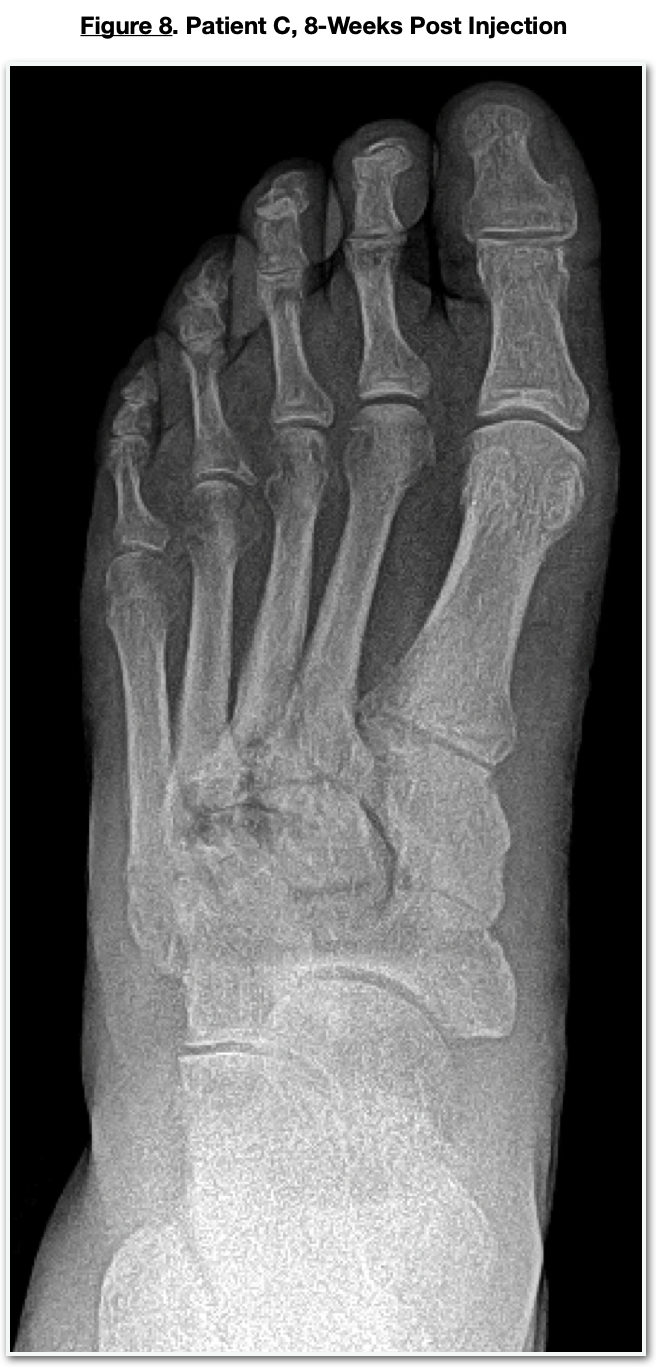

The patient presented to the office with a swollen, painful left midtarsal joint. X-rays (Figure 6) revealed numerous subchondral cysts with osteolysis at the lateral midtarsal joint consistent with an acute Charcot neuroarthropathy. CT confirmed the Charcot arthropathy showing multiple subchondral cysts (Figure 7) and subchondral edema. He was immobilized with a diabetic CAM boot. Follow-up X-rays revealed an increase in osteolysis and a slight lateral shift of the lateral column, indicating a progression of the acute neuroarthropathic process. He chose to have percutaneous placental tissue injections into the acute areas of the midfoot. This procedure was done under fluoroscopic guidance with placental cells injected into the metatarsal bases at the cystic and intercuneiform regions. He was immobilized with the CAM boot, and this area progressed uneventfully to a stable but arthritic construct. (Figure 8) The acute inflammatory component of the Charcot subsided within days of the injection.